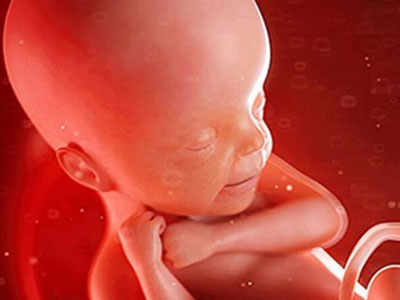

其实孩子还是胎宝宝时,就已经开始各种“搞怪”了,这也是为什么咱们能感受到他们的存在。但如果你以为胎宝宝只会这些就错了,他们在妈妈肚子里干的事情多着呢!

扮鬼脸

胎宝宝在娘胎里就是“戏精”:吸吮手指、啃脚丫、吧唧嘴、抠鼻子、吐舌头、微笑、皱眉......表情贼丰富了!妈妈第一次给胎宝宝做四维彩超时有没有惊讶到?我那会儿开心死了!原来,他很早就学会表达自己的感受了,还真是人精!

原来胎宝宝在妈妈肚子里竟有这么多小动作!虽然这些我们有的能感觉到,有的不能,但只要想到此刻宝贝可能在做鬼脸、撅屁股等,然后学到的东西越来越多,孕期的各种不适就都不算什么了。宝贝,快快长大哦,妈妈期待见到你的那天!